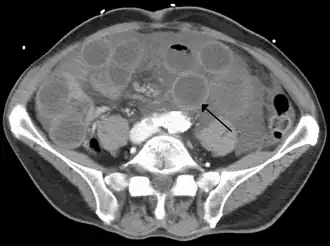

TC de una isquemia de intestino delgado debida a trombosis de la vena mesentérica superior. Se muestra el intestino dilatado y la pared engrosada. | ||